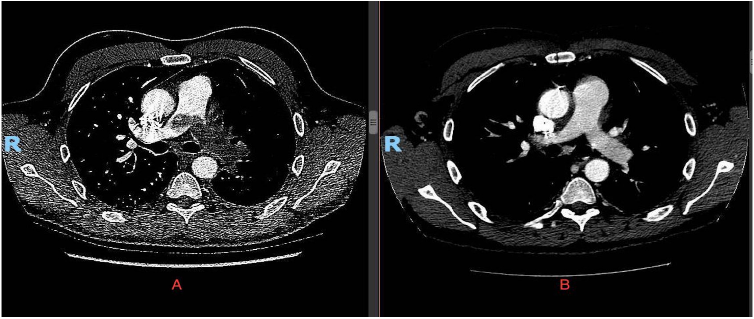

復(fù)查胸部 CT 提示左肺動(dòng)脈充盈缺損較前擴(kuò)大,伴分支血管充盈缺損影像(圖 1)。左肺邊緣呈片狀楔形陰影,提示肺梗死(圖 2)。

考慮抗凝無(wú)效,遂決定實(shí)施左肺血栓切除術(shù),術(shù)后病理確診惡性梭型細(xì)胞瘤。FISH 提示 MDM2 擴(kuò)增陽(yáng)性,AE1/3、MSA、desmin、caldesmin、EMA、CD99、CD34、S100 蛋白、STATS 免疫染色均陰性。